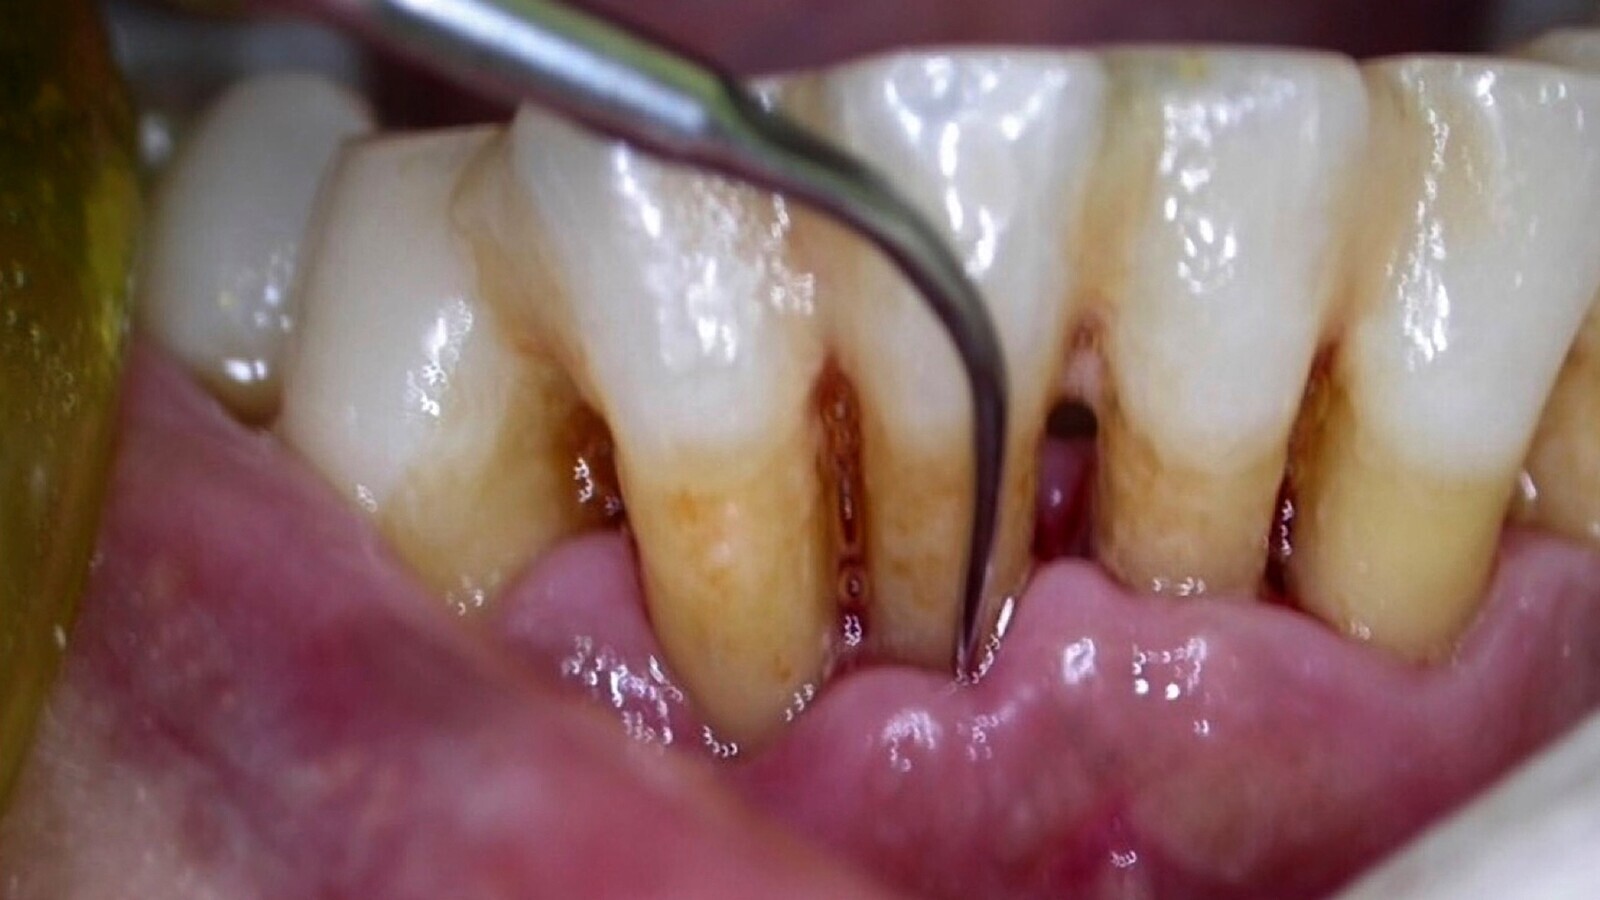

Una vez que el paciente se cataloga de bajo, medio o alto riesgo de desarrollar problemas bucodentales (acumulo de placa, caries radiculares), se le incluirá en un programa. El consejo es realizar visitas inicialmente cada 2 meses en aquellos pacientes de alto riesgo y como máximo cada 6 meses en los de bajo riesgo. En cada una de las visitas, el odontólogo hace una revisión, si hay que realizarle algún tratamiento y valoración de su evolución, y el/la higienista dental procede a realizarle una limpieza nuevamente y aplicar el barniz o gel fluorados que le indique el odontólogo (Figs. 5, 6 y 7). Posteriormente, se reforzarán las instrucciones para la limpieza diaria por el propio paciente, personal auxiliar cuidador o familiares del paciente.

Figura 5. Se deben realizar limpiezas con ultrasonidos y/o curetas, según las necesidades del paciente.